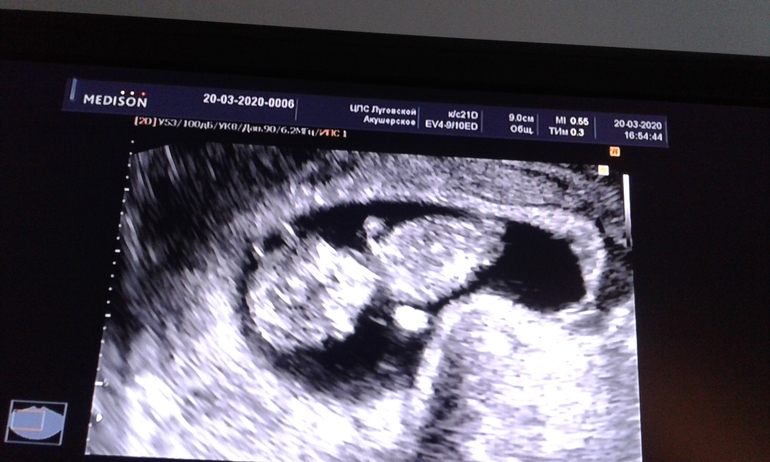

Вот недавно также была в похожей ситуации - стрэс, нервы, паника. срок был чуть более 9 недель. Еще и накрутила себя что с малышом наверно не все ок. Пошла на узи. Узист сразу мне вопрос " вы сильно перенервничали? Вот, смотрите на Ваше ПЯ". смотрю на монитор, ПЯ изогнуто. Фото прилагаю (тонус или гипертонус. Я не запомнила, как она сказала). На предыдущем узи было идеально ровное. Узист меня успокоила, что СБ +, малыш ок. Я расслабилась, заулыбалась И на глазах тонус начал уменьшаться. вот такие прямые мгновенные последствия от нервов на наших малышей. Девочки, старайтесь забить на все. Нужно спокойствие и позитив для ребеночка